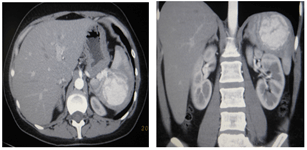

The abdominal organs (Figure 3) revealed a mass, measuring 6.4x6.7 cm, in the upper pole of the spleen. The lesion accumulated a contrast agent in the arterial phase of the study; in the venous and delayed phase, it became isodental. Conclusion: Spleen hemangioma.

Figure 3: Spleen hemangioma, MSC-tomograms in the arterial phase of the study, A) axial and B) frontal scans.